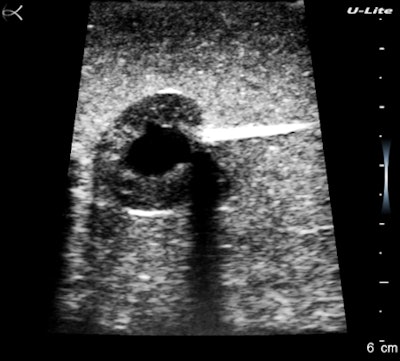

Look at the magnified cherry images below. They hold together beautifully, and there is an impressive visible grayscale intensity range. The fluid cleft and the pitted center of the cherry have sharp clear boundaries, and there is an acoustic shadow effect deep to the cherry. These settings were mainly for contrast resolution, which is the most important performance factor for recognizing and excluding pathology. I could have done better with near-field gain and I fixed that later.